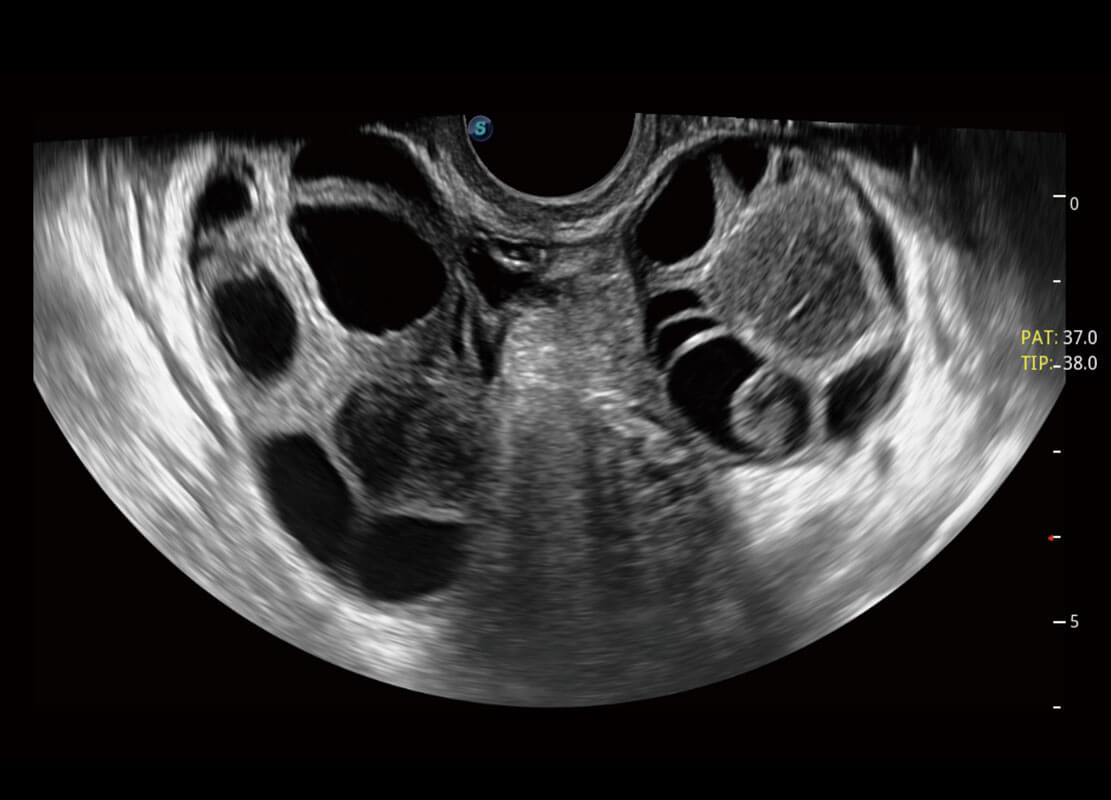

生殖健康

P60优异的图像质量搭载专科探头,在妇科基础疾病的诊断、卵泡生长的监测、输卵管通畅情况的判别等方面为您提供生殖应用方案。

• 腔内妇科-宫腔分离

• 腔内妇科-卵巢

• 腔内三维-宫内节育器

• 腔内三维-光影成像